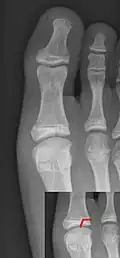

Salter–Harris III fracture of big toe proximal phalanx. -